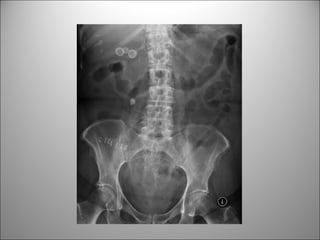

DETECCIÓN DE CUERPOS EXTRAÑOS

 SÓLO LOS RADIO-OPACOS